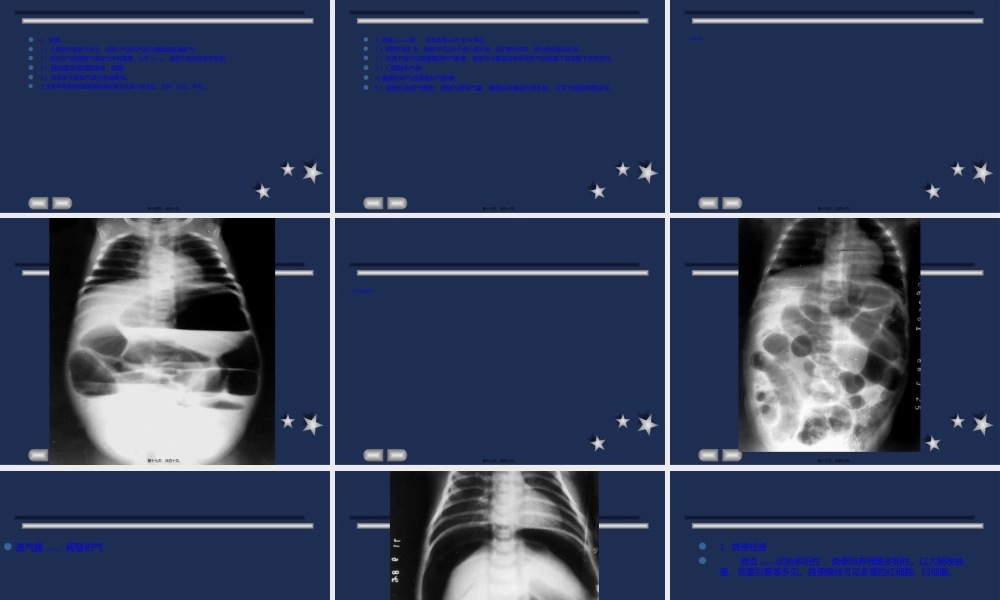

新生儿坏死性小肠(xiǎocháng)结肠炎第一页,共四十页。查房目标1掌握新生儿坏死性小肠结肠炎的概念2掌握新生儿坏死性小肠结肠炎的临床表现3掌握新生儿坏死性小肠结肠炎的治疗及相关护理(hùlǐ)措施第二页,共四十页。拟题问题新生儿坏死性小肠结肠炎的定义(dìngyì)新生儿坏死性小肠结肠炎的临床表现该患儿的护理诊断及护理措施第三页,共四十页。病史患儿,男,13小时。因腹胀、呕吐、解鲜血便1小时入院。系G1P1孕36+6周,自然分娩,出生时Apgar评分10分,哭声可,面色红,生后混合喂养,奶量少,生后13小时患儿出现腹胀,吐黄绿色粘液,并排(bìngpái)血便为进一步治疗收入。第四页,共四十页。病史入院查体:T37.8度HR:126次/分R:42次/分BP:58/32mmHg神志清,反应存,前囟平,面唇红,三角区青,哭声可,腹胀,脐结扎(jiézā),肢端温,活动存,解血样便一次。第五页,共四十页。病史治疗:禁食,胃肠减压一级护理(hùlǐ),心电监护优立新,复达欣针抗感染,维生素K1止血,补液营养支持治疗第六页,共四十页。血常规及血凝分析,活化部分凝血活酶时间(shíjiān)APTT-sec58.00s,参考时间(shíjiān)APTT-Ref28.50S,血红蛋白137克每升,红细胞3.77*10的12次方每升,血气分析示:PH7.103,PCO233.7mmHg,BE-19mmol/L,HCO310.7mmol/L,GLU453mg/dl,Na127mmol/L,K4.6mmol/L,Hb14.3g/dl第七页,共四十页。便隐血试验阳性。粪便和血培养(péiyǎng)可阳性,以杆菌多见。X线检查肠胀气:小肠为主,有多个液平(立位腹平片),肠曲间距增宽。第八页,共四十页。概念是围生期的多种致病因素导致的肠道疾病(jíbìng),多在出生后2周内发病,严重威胁新生儿的生命。第九页,共四十页。病因①肠道供血不足,如新生儿窒息、肺透明膜病、脐动脉插管、红细胞增多症、低血压、休克等;②饮食因素(yīnsù),如高渗乳汁或高渗药物溶液可损伤肠粘膜,食物中的营养物质有利于细菌生长和碳水化合物发酵产生氢气;③细菌感染,如大肠杆菌、克雷白杆菌、绿脓杆菌、沙门氏菌、梭状芽胞杆菌等过度繁殖,侵入肠粘膜造成损伤,或引起败血症及感染中毒性休克加重肠道损伤第十页,共四十页。腹胀:首发症状,先有胃排空延迟,而后全腹胀,肠鸣音减弱或消失临床表现病情进展迅速、感染中毒症状严重腹泻、血便呕吐:可有胆汁或咖啡样物其他:隐匿发生者表现非特异性症状第十一页,共四十页。IIIA期IIB期IIA期I期喂养(wèiyǎng)不耐受、反复胃潴留...

2、本站所有内容均由合作方或网友上传,本站不对文档的完整性、权威性及其观点立场正确性做任何保证或承诺!文档内容仅供研究参考,付费前请自行鉴别。